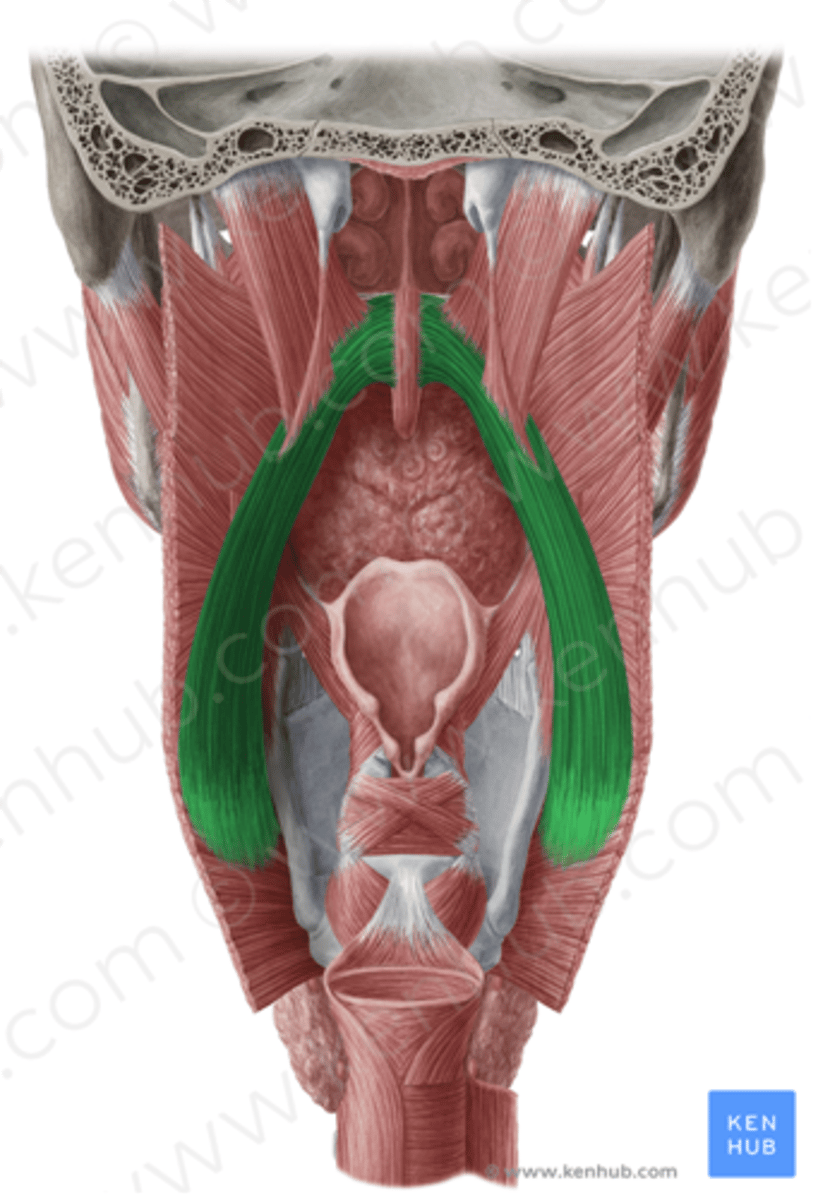

Palatopharyngeus Figure

Palatopharyngeus Description

Also known as Pharyngopalatine

Posterior faucial pillar

- Longer muscle

Origin

- Soft palate

Course

- Superior through posterior faucial pillar

Insertion

- Lateral walls of pharynx, thyroid cartilage

Action

- Principally to guide material through pharynx

- May contribute to palatal lowering

- May contribute to VP seal